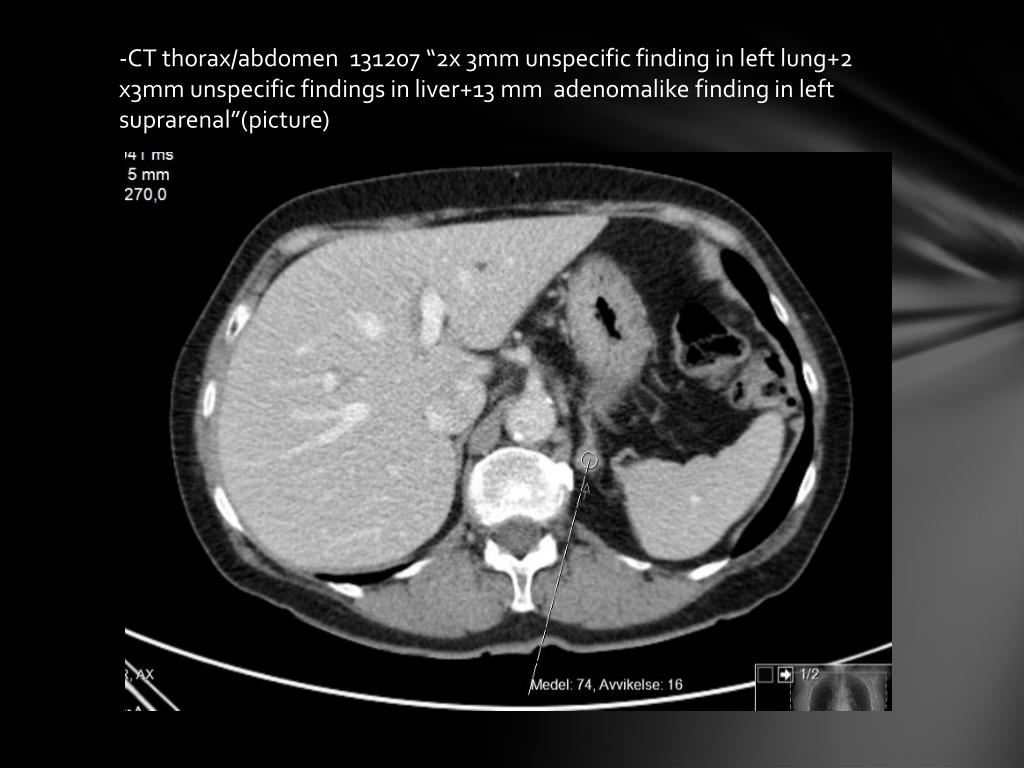

3. -CT thorax/abdomen 131207 “2x 3mm unspecific finding in left lung+2 x3mm unspecific findings in liver+13 mm adenomalike finding in left suprarenal”(picture)